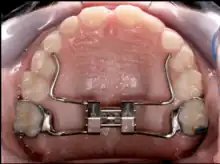

A palatal expander is a device in the field of orthodontics which is used to widen the upper jaw (maxilla)[1] so that the bottom and upper teeth will fit together better.[2][3] This is a common orthodontic procedure. The use of an expander is most common in children and adolescents 8–18 years of age. It can also be used in adults, although expansion is more uncomfortable and takes longer in adults. A patient who would rather not wait several months for the end result achieved by a palatal expander may be able to opt for a surgical separation of the maxilla. Use of a palatal expander is most often followed by braces to then straighten the teeth.

Rapid palatal expansion (RPE) or Rapid Maxillary Expansion (RME) is an expansion technique where expansion of 0.5 mm to 1 mm is achieved each day until the posterior crossbite is relieved. The expander works by turning a key inside the center of the expander. The turn of this key will push the arms of the expander.

For stability purposes, the RPE usually remain in the patient's mouth anywhere between 3–6 months, but this time may vary between patients. This is often known as "six month retention period" during which the bone fills the gap in the maxilla that was created by the expansion process. To prevent any type of relapse, a retainer is given to the patient to keep the teeth in proper alignment.[6] RPE can be tooth supported, bone supported or both.

The expansion process usually results in a large gap between the patient's two top front teeth, often known as diastema. This gap is closed naturally and the teeth may overlap which leads to braces being needed. Some may develop a large space while others do not develop a space at all. It usually takes a week or two for one to adjust to eating and speaking after first receiving the rapid palatal expander. This process requires patients to turn the expansion screw themselves to widen the expander. For expansion that is not managed by the patient and on the lower jaw, a bionator appliance may be a more suitable alternative.